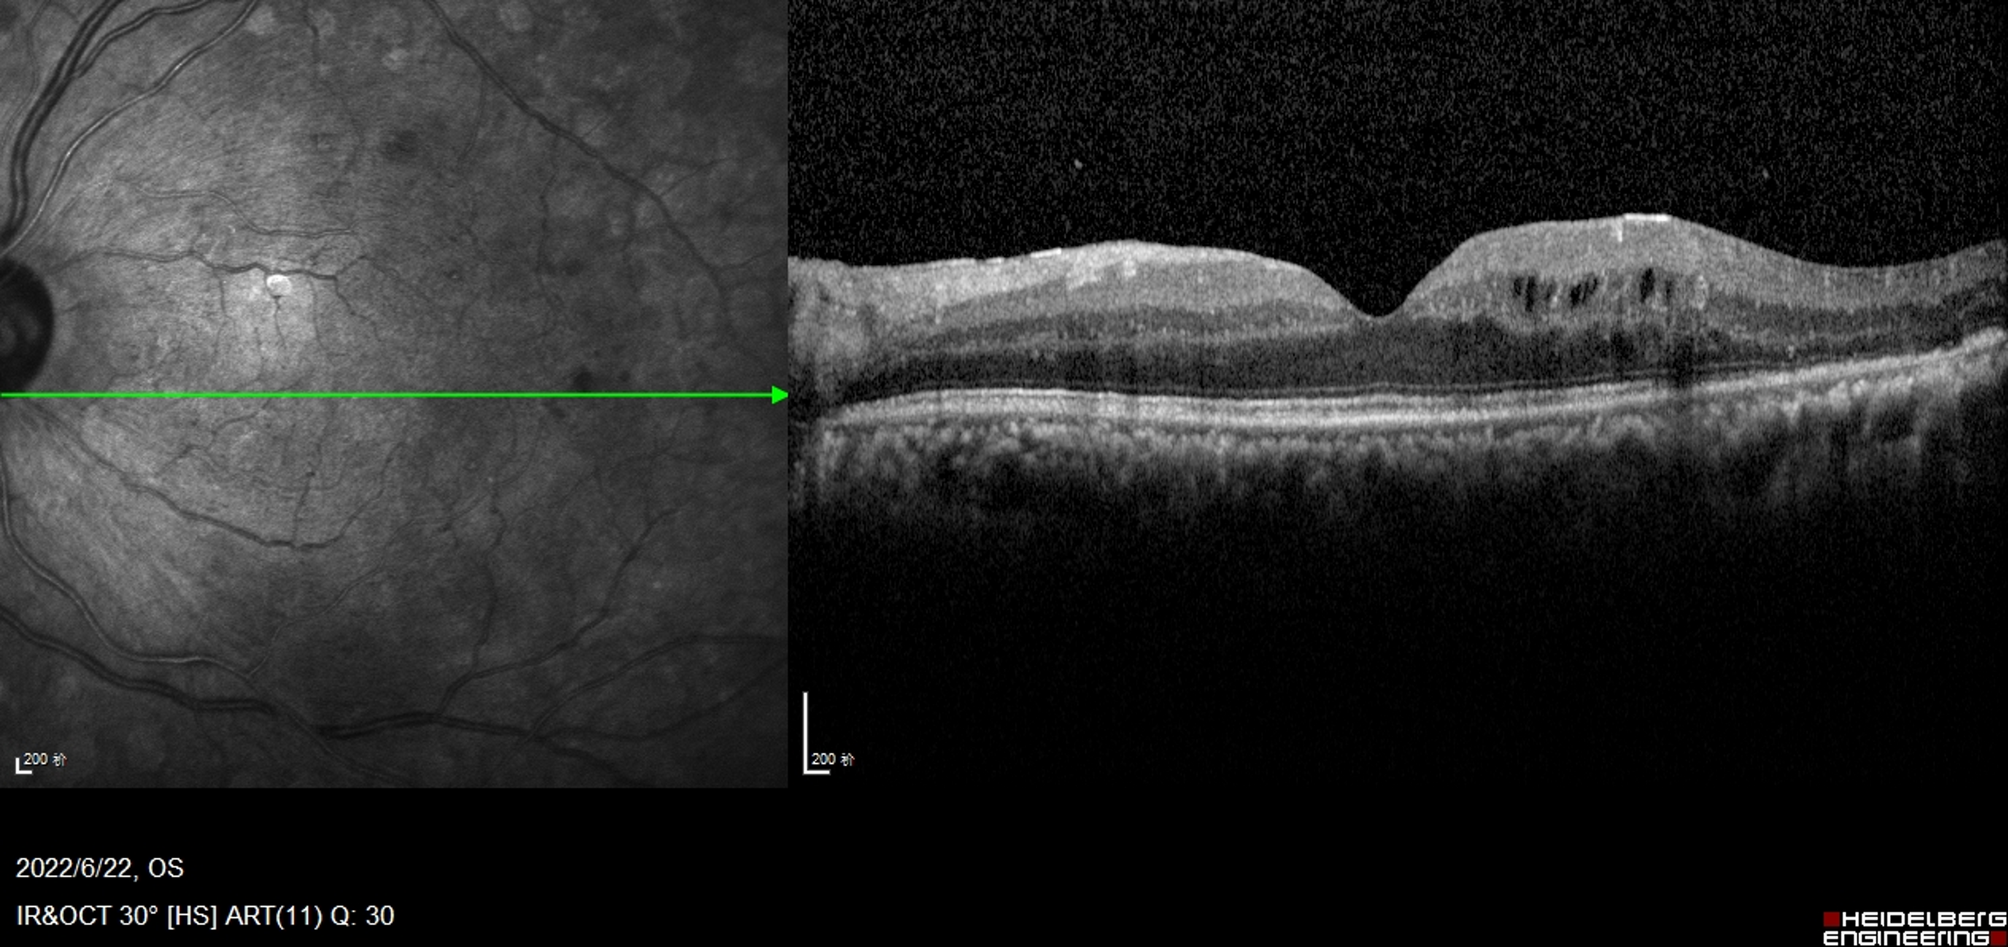

Fig. 1

Early DME Multiple perifoveal cystoid spaces in the INL, the OPL, with mild thickening of the temporal area of foveal, absence of any visible adhesion or traction between vitreous cortex and retina, hyperreflective foci are less than 30 in number. The TCED-HFV grading is T = 1, C = 2, E = 0, D = 0, H = 0, F = 0, and V = 0.